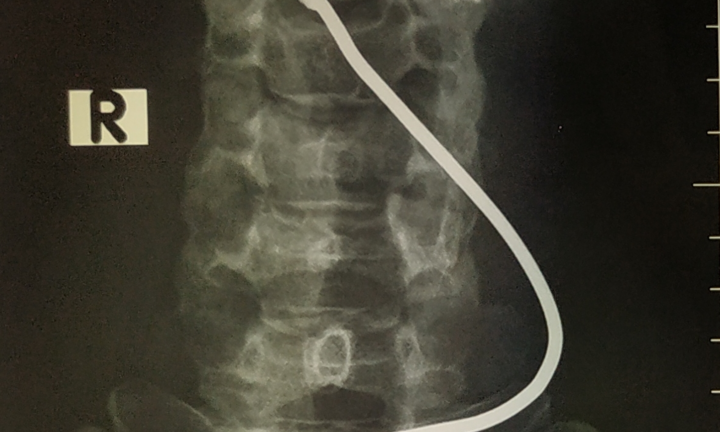

Người đàn ông nhập viện trọng tình trạng tỉnh táo, vùng cổ có vết thương thanh quản 0,5cm do dị vật là thanh sắt bắn vào, gây tổn thương sụn giáp.